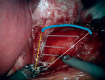

Combining transoral fundoplication and robotic cruroplasty: a novel robotic-assisted endoscopy